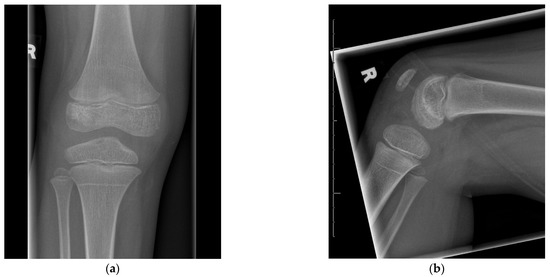

| Author(s) | Year | n (*) | Age | Knee Involvement | Therapeutic Management | F/U | Outcome |

|---|---|---|---|---|---|---|---|

| Green at al. [14] | 1981 | 2 (8) | 2–4 yrs | Lesions extended to articular cartilage without damage to cartilage itself | Curettage, sampling (6× negative), oxacillin (2× Staph. aureus) | 2–8 yrs | No evidence of damage to physis or joint |

| Rosenbaum & Blumhagen [28] | 1985 | 7 (9) | 21 mo–9 yrs | N/A | Arthrocentesis (5) and antibiotics | N/A | N/A |

| Sorensen et al. [21] | 1988 | 1 (3) | 4 yrs | Joint effusion | Curettage and bone grafting, cephalexin | 3 yrs | Normal |

| Longjohn et al. [19] | 1995 | 1 (1) | 4 yrs | Pain after initial trauma, later moderate effusion | Aspiration, nafcillin, arthrotomy, irrigation, curettage | 6 yrs | Normal function, but radiographically flattening of LFC |

| Rasool [25] | 2001 | 1 (2) | N/A | Lesion did not involve articular surface | Curettage, biopsy, culture, immobilization and antibiotics | 2 yrs | Normal |

| Kao et al. [16] | 2003 | 2 | 27/28 mo | Joint aspirate negative | Arthrotomy/curettage and antibiotics | 6–16 mo | Normal |

| Abdelgawad et al. [24] | 2007 | 1 | 17 mo | Mild knee effusion | Repeated fluoro- and CT-guided abscess drainage (3×), antibiotics | N/A | Normal |

| Saisu et al. [8] | 2008 | 2 ‡ | 2–5 yrs | Chronic femoral/tibial osteomyelitis (not only epiphyseal infection) | Endoscopic surgery with drilled dual opposing insertion paths | 3–4.5 yrs | Normal |

| Hara et al. [26] | 2013 | 1 | 26 mo | Local heat and motion pain in the knee | Cefazolin (1200 mg/d), oral cefdinir (150 mg/d) | 2 yrs | No recurrence |

| Yoo et al. [10] | 2014 | 6 (8) | 12–25 mo | Mycobacterial infections, abscess extended outside physis in 7/8 cases | Antibiotics, surgical drainage/curettage when the abscess necessitated decompression (4), or not responsive to antibiotics (4), antimycobacterial chemotherapy | 4.1 yrs | Focal physeal damage in 5, 1 with growth disturbance |

| Shah et al. [9] | 2020 | 12 | 3–14 yrs | 9/18 had penetration of the joint | Open aggressive surgical treatment w/arthrotomy and antibiotics | mean 5.5 (2–11 yrs) | Joint destruction if tubercular pathogen (n = 4) |